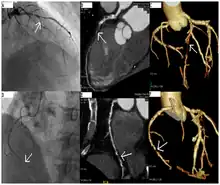

Coronary catheterization is one of the several cardiology diagnostic tests and procedures. Specifically, through the injection of a liquid radiocontrast agent and illumination with X-rays,[1] angiocardiography allows the recognition of occlusion, stenosis, restenosis, thrombosis or aneurysmal enlargement of the coronary artery lumens; heart chamber size; heart muscle contraction performance; and some aspects of heart valve function. Important internal heart and lung blood pressures, not measurable from outside the body, can be accurately measured during the test. The relevant problems that the test deals with most commonly occur as a result of advanced atherosclerosis – atheroma activity within the wall of the coronary arteries. Less frequently, valvular, heart muscle, or arrhythmia issues are the primary focus of the test.

During coronary catheterization (often referred to as a cath by physicians), blood pressures are recorded and fluoroscopy (X-ray motion picture) shadow-grams of the blood inside the coronary arteries are recorded. In order to create the X-ray pictures, a physician guides a small tube-like device called a catheter, typically ~2.0 mm (6-French) in diameter, through the large arteries of the body until the tip is just within the opening of one of the coronary arteries. By design, the catheter is smaller than the lumen of the artery it is placed in; internal (intra-arterial) blood pressures are monitored through the catheter to verify that the catheter does not block blood flow (as indicated by "dampening" of the blood pressure).

The catheter is itself designed to be radiodense for visibility and it allows a clear, watery, blood compatible radiocontrast agent, commonly called an X-ray dye, to be selectively injected and mixed with the blood flowing within the artery. Typically 3–8 cc of the radiocontrast agent is injected for each image to make the blood flow visible for about 3–5 seconds as the radiocontrast agent is rapidly washed away into the coronary capillaries and then coronary veins. Without the X-ray dye injection, the blood and surrounding heart tissues appear, on X-ray, as only a mildly-shape-changing, otherwise uniform water density mass; no details of the blood and internal organ structure are discernible. The radiocontrast within the blood allows visualization of the blood flow within the arteries or heart chambers, depending on where it is injected.

If atheroma, or clots, are protruding into the lumen, producing narrowing, the narrowing may be seen instead as increased haziness within the X-ray shadow images of the blood/dye column within that portion of the artery; this is as compared to adjacent, presumed healthier, less stenotic areas.

CT angiography can act as a less invasive alternative to Catheter angiography. Instead of a catheter being inserted into a vein or artery, CT angiography involves only the injection of a CT-visible dye into the arm or hand via an IV line. CT angiography lowers the risk of arterial perforation and catheter site infection. It provides 3D images that can be studied on computer, and also allows measurement of heart ventricle size. Infarct area and arterial calcium can also be observed (however those require a somewhat higher radiation exposure). That said, one advantage retained by Catheter angiography is the ability of the physician to perform procedure such as balloon angioplasty or insertion of a stent to improve blood flow to the artery.[7]